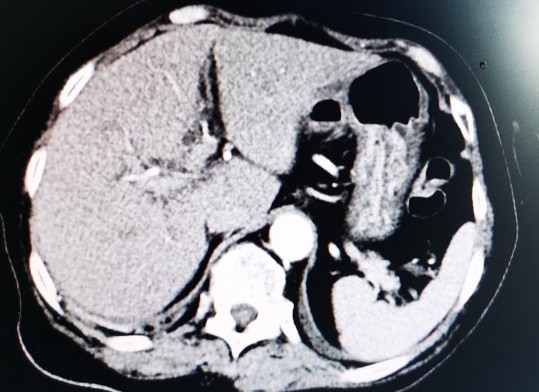

黄婶的肝脏,左右分明,左右肝均萎缩,脾大

萎缩的右肝发展成了肝癌